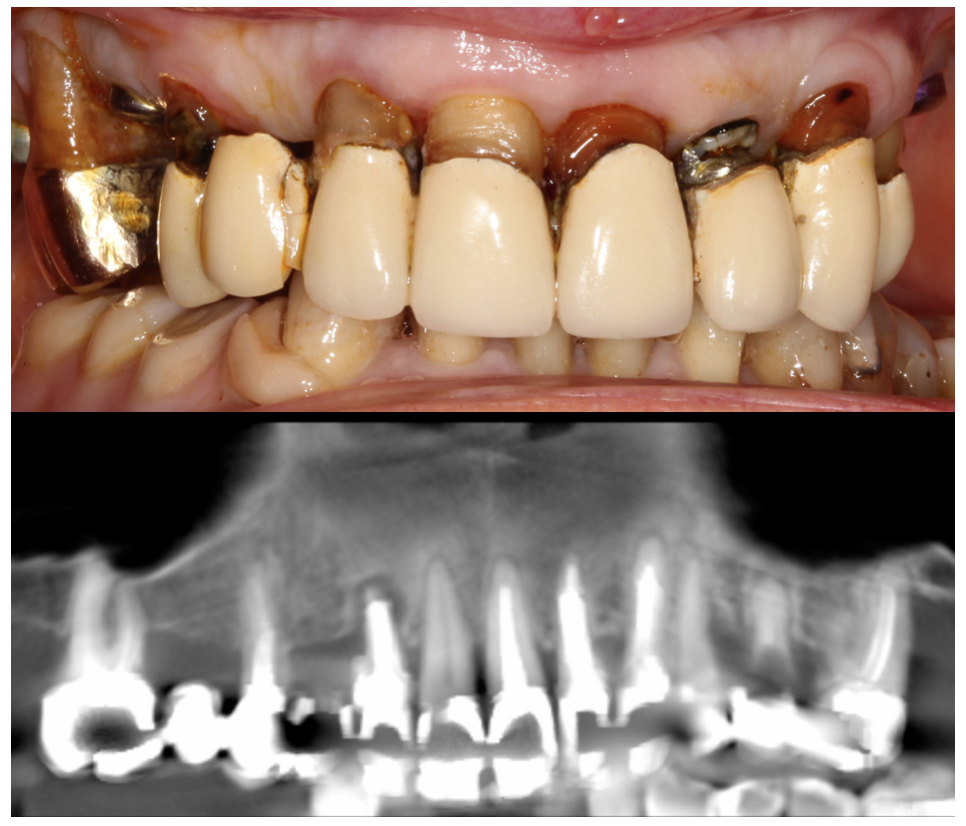

Madame B. âgée de 59 ans, est adressée pour l’absence des dents 21 et 22 remplacées par une prothèse amovible inconfortable et inesthétique. Le sourire très gingival laisse apparaître des défauts disgracieux.

Un examen clinique approfondi et une étude cône beam montrent une situation dégradée sur beaucoup de dents et une restauration complète est envisagée au maxillaire.

Par ailleurs, le découvrement de la lèvre créant un sourire très inesthétique, la restauration implanto-prothétique devra tenir compte de cet aspect très important pour la patiente.

Pour mémoire cas au départ :